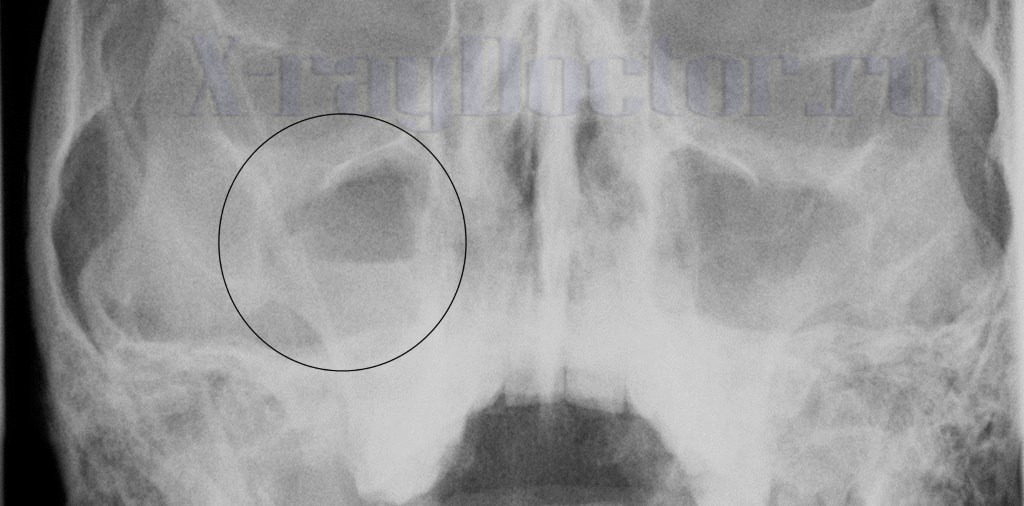

На снимке в носоподбородочной проекции гайморит визуализируется в виде затемнений с верхним горизонтальным уровнем в нижней и средней трети. При аллергических болезнях могут визуализироваться подушкообразные выпячивания слизистой оболочки. Они представляют собой рентгенологические синдромы «плюс-тень» (дополнительное образование средней или высокой интенсивности).

Рентгенография носовых пазух описывается рентгеновским симптомом «затемнение». Увидев тень в проекции придаточных образований, врач-рентгенолог предполагает гайморит. При наличии полости, заполненной жидким содержимым, можно предположить кисту гайморовой пазухи.

На рентгеновском снимке при гайморите видно затемнение с верхним горизонтальным уровнем в большинстве случаев. На начальных стадиях болезни на рентгенограмме можно определить незначительные скопления инфильтративной жидкости.

На классическом рентгеновском снимке виден четкий уровень жидкости, который не оставляет сомнений в диагностике болезни. Иногда на рентгенограмме видны четкие тени, которые прослеживаются по краям.